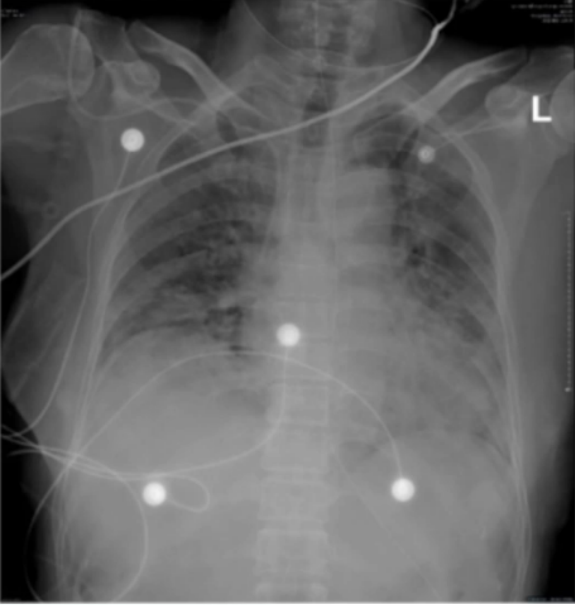

患者于RICU治疗5天, 气喘缓解不明显, 呼吸频率>30次/分, 氧合指数较前明显下降(124 mmHg)。床旁胸片可见双肺广泛渗出(2)

图片

2  患者床旁胸片(2022-12-27)